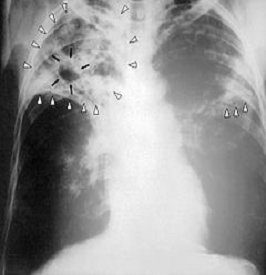

Рис.1 Туберкулез легких

Рис.2 Легочные проявления туберкулёза